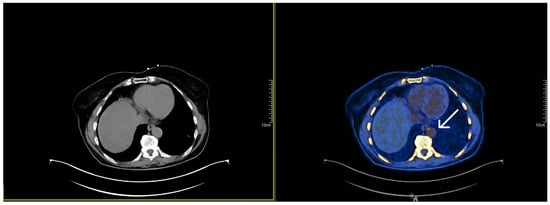

2.2. Imaging Microcalcification with 18F-Sodium Fluoride (NaF)